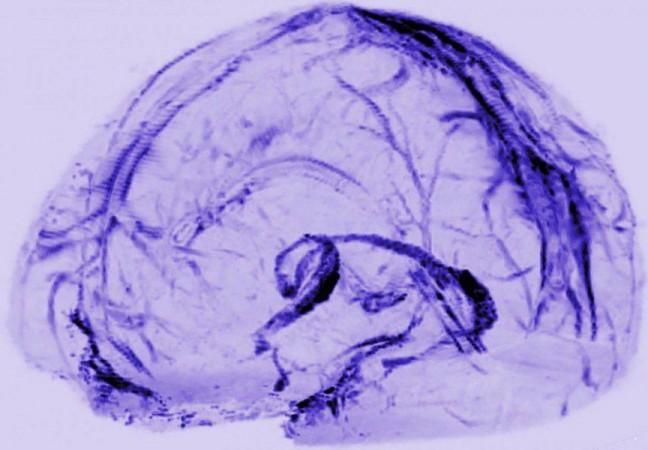

To look for the vessels, Dr. Reich's team used MRI to scan the brains of five healthy volunteers who had been injected with gadobutrol, a magnetic dye typically used to visualise brain blood vessels damaged by diseases, such as multiple sclerosis or cancer. The dye molecules are small enough to leak out of blood vessels in the dura but too big to pass through the blood-brain barrier and enter other parts of the brain.

At first, when the researchers set the MRI to see blood vessels, the dura lit up brightly, and they could not see any signs of the lymphatic system. But, when they tuned the scanner differently, the blood vessels disappeared, and the researchers saw that dura also contained smaller but almost equally bright spots and lines which they suspected were lymph vessels. The results suggested that the dye leaked out of the blood vessels, flowed through the dura and into neighbouring lymphatic vessels.

To test this idea, the researchers performed another round of scans on two subjects after first injecting them with a second dye made up of larger molecules that leak much less out of blood vessels. In contrast with the first round of scans, the researchers saw blood vessels in the dura but no lymph vessels regardless of how they tuned the scanner, confirming their suspicions.

They also found proof for blood and lymph vessels in the dura of autopsied human brain tissue. Moreover, their brain scans and autopsy studies of brains from non-human primates confirmed the results seen in humans, suggesting the lymphatic system is a common feature of mammalian brains.